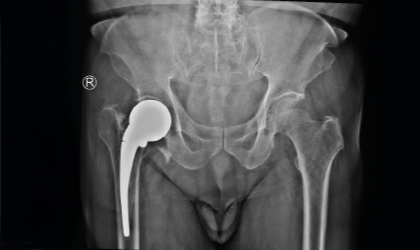

This 83 year old gentle man had a hip fracture 25 years ago. This became painful recently. He had an interesting (to the surgeons!) complication with a fracture of the stem in 3 places. This was revised to a total hip replacement. We used a longer stem to bypass the defects. He is mobile with a stick.

Post-surgery, he recovered well and is now independently mobile using a walking stick, regaining comfort and stability after years of discomfort.

Despite his age and the complexity of the case, the revision surgery was a success. With restored mobility and reduced pain, he enjoys independence in his daily activities.